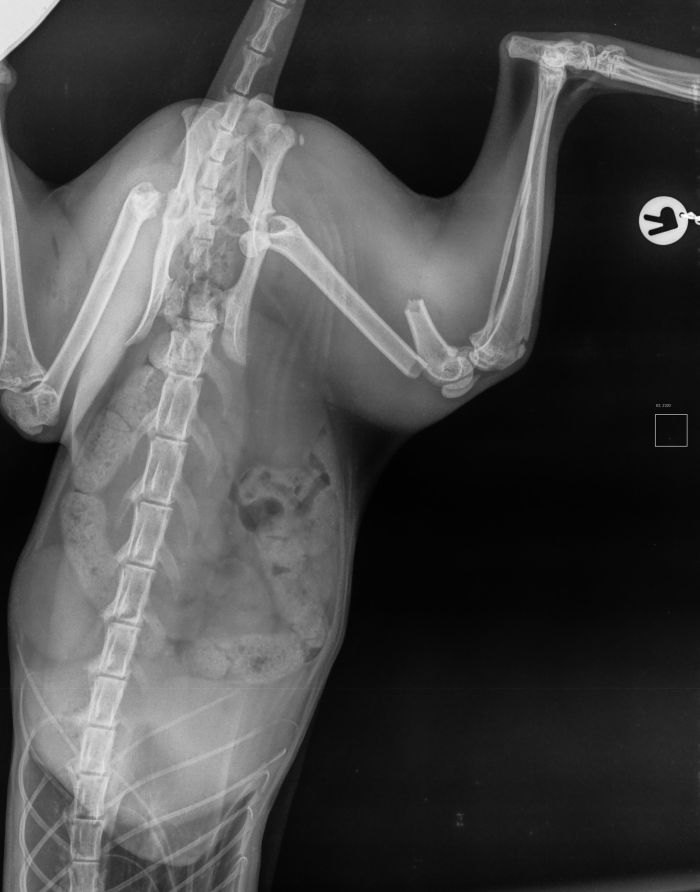

Fixateur externe

Hierbei werden Pinstangen durch die Haut hindurch in die jeweiligen Knochenfragmente gebohrt / in diesen Fragmenten verankert. An den Pinstangen wird dann aussen quer zu den gesetzten PinStangen entweder eine Längsstange oder Kunststoffüberbrückungen angebracht. Die Verwendung eines Fixateur hat seine Vor- und Nachteile die im jeweiligen Einzelfall durch unseren Operateur mit Ihnen besprochen werden.

Fall 1